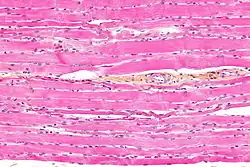

Les myocytes sont limités par le sarcolemme, constitué d'une membrane plasmique et d'une lame basale. Chaque fibre musculaire apparaît par fusion de plusieurs cellules musculaires (c'est un syncytium). Une fibre musculaire a donc plusieurs noyaux, dont le nombre dépend de l'activité musculaire. Ces noyaux, ovoïdes, sont situés en périphérie de la cellule, sous le sarcolemme. À proximité des noyaux, on trouve des vacuoles lipidiques et des vacuoles de myoglobine (qui donnent leur couleur rouge aux muscles). Le cytoplasme (appelé sarcoplasme dans les cellules musculaires) est abondant : les myofibrilles (unités contractiles du muscle) y sont assemblées en colonnettes dites de Leydig (stries latérales lorsqu'on observe au microscope). Elles occupent 80 % du volume des myocytes.

Les myofibrilles sont composées de filaments épais (composés de myosine) et de filaments fins (composés d'actine, de troponine et de tropomyosine). En coupe longitudinale, les myofibrilles présentent une striation transversale due à la présence de zones claires et de zones sombres :

- la zone sombre est la bande A (pour anisotrope), qui résulte de la condensation de molécules de myosine (environ 300 molécules de myosine par filament) ;

- une zone médiane plus claire : la zone H (hell qui signifie clair en allemand), qui résulte d'un aménagement particulier de la myosine, en forme de crosse de hockey (avec une tête et une tige). Les tiges se recouvrent les unes les autres, les têtes se regroupent en hélice pour former la strie M (Mittelscheibe signifie littéralement « tranche/coupe du milieu » en allemand) ;

- la bande I (pour isotrope), divisée en 2 par la strie Z (Zusammen signifie « ensemble » en allemand, elle correspond en effet à la jonction entre deux sarcomères), est constituée par 3 autres protéines contractiles disposées en filaments fins.

La strie Z sépare deux sarcomères (qui sont les unités fonctionnelles contractiles). Un sarcomère est composé d'une demi-bande I, d'une bande A et d'une deuxième demi-bande I. Les myofilaments fins s'intercalent entre les myofilaments épais, sauf au niveau de la strie Z (constituée de myofilaments fins seulement) et la strie H (constituée uniquement de tiges de myosine). Lors de la contraction, le sarcomère se raccourcit (de 20 à 50 %), les zones I et H se rétrécissent, alors que la zone A reste inchangée. Les filaments fins glissent entre les filaments épais vers la ligne médiane du sarcomère, et attirent la strie H. Il y a aussi une autre strie appelée M qui se situe au milieu de la zone H. Cette strie M est constituée de ponts protéiques qui vont réunir les myofilaments épais et jouer un rôle de cohésion.